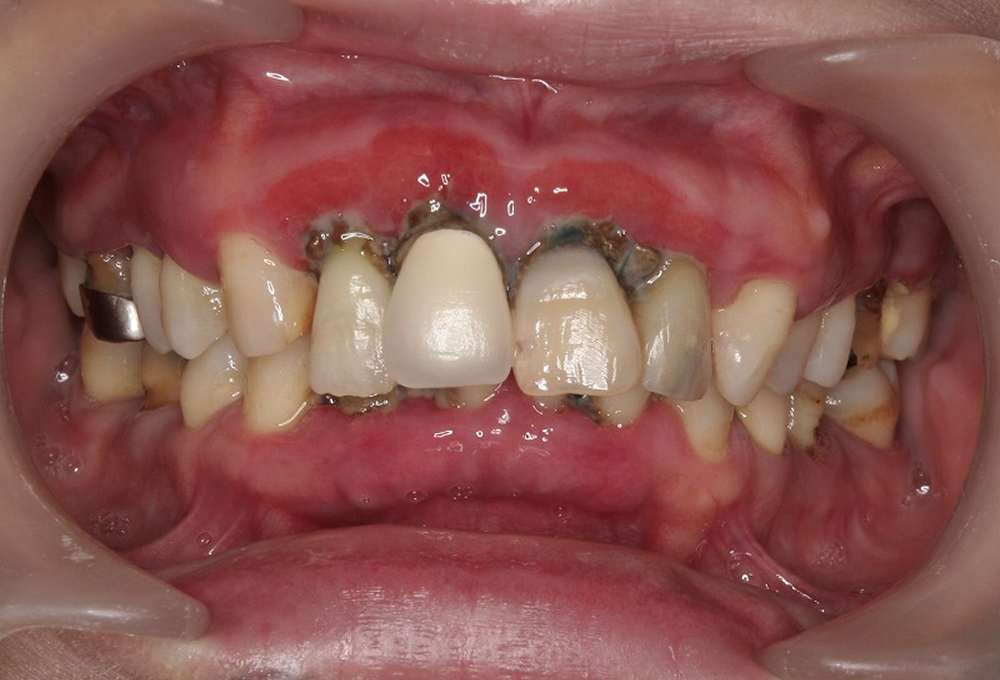

①術前 プラークコントロール不良 歯周炎